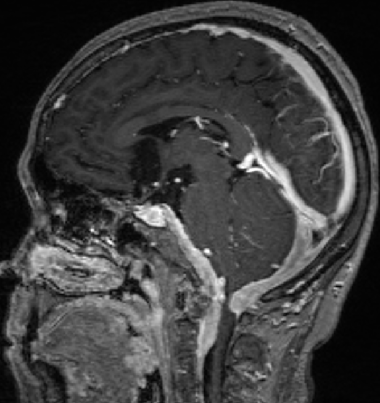

2014-10-17 CT

仍时有前额部疼痛,程度轻,调压190—200